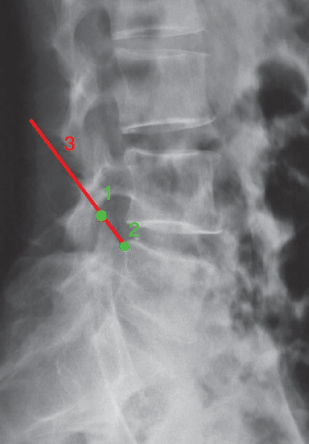

CT显示L4/5节段的椎间盘突出脱垂型(图1)。MRI示L4/5节段的椎间盘突出到Ⅲ层面(图2)。红外热成像显示左侧下肢的皮温明显低于右侧(图3)。

图1 CT轴位片L4~5节段的椎间盘突出:脱垂型

图6 腰椎DR侧位片1.上关节突尖;2.L5椎体后上缘;3.穿刺角度线:上关节突尖与椎体后上缘的连线。